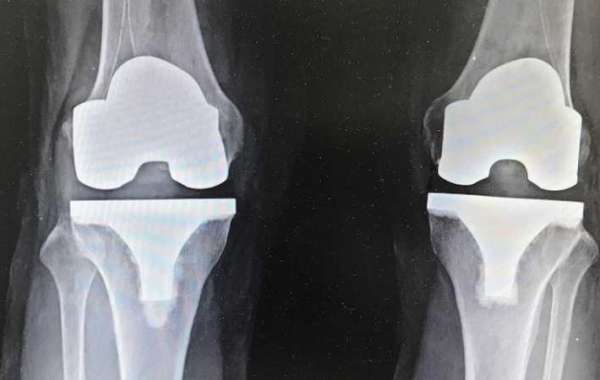

Knee replacement surgery is also known as knee arthroplasty or total knee replacement. Severe knee injury or arthritis may cause this type of surgery. Dr. Ashwini Gaurav is one of the leading knee replacement surgeon in Patna. The goal of knee replacement surgery is to reshape the knee joints and relieve knee pain.

After that we will conduct our surgery procedure as per the requirements. We will remove the damaged surfaces of the knee joint and replace with the prosthesis. The knee prosthesis made up of metal and plastic. The most common type of artificial knee prosthesis is a cemented prosthesis. Once the surgery done, patient can walk from the very next day and take a few weeks to get back to normal life.